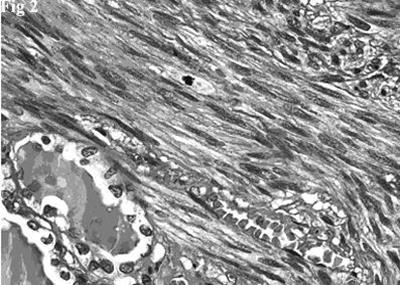

Figure 2.Hematoxylin and eosin stain showing a fascicle of spindle cells contiguous to residual thyroid follicles. The spindle cells posses blunt-ended, moderately hyperchromatic nuclei. A mitotic figure is evident (top, center).

Histologically there was a proliferation of elongated spindle-shaped cells, arranged in interweaving fascicles of varying sizes, intersected at right angles, having blunt-ended, cigar-shaped, centrally located, nuclei. Nuclear hyperchromatism and pleomorphism were generally mild and, occasionally, moderate. The cells had an abundant cytoplasm that varied tinctorially from pink to red in sections stained with hematoxylin-eosin. There was no coagulative tumor cell necrosis. Mitotic figures were easily identified (10 mitoses per 10 HPF). Rare and scattered residual thyroid follicles were surrounded and deformed by the neoplastic fascicles (Figure 2). The follicles, with central colloidal deposits, were lined by flattened or cuboidal epithelial cells.